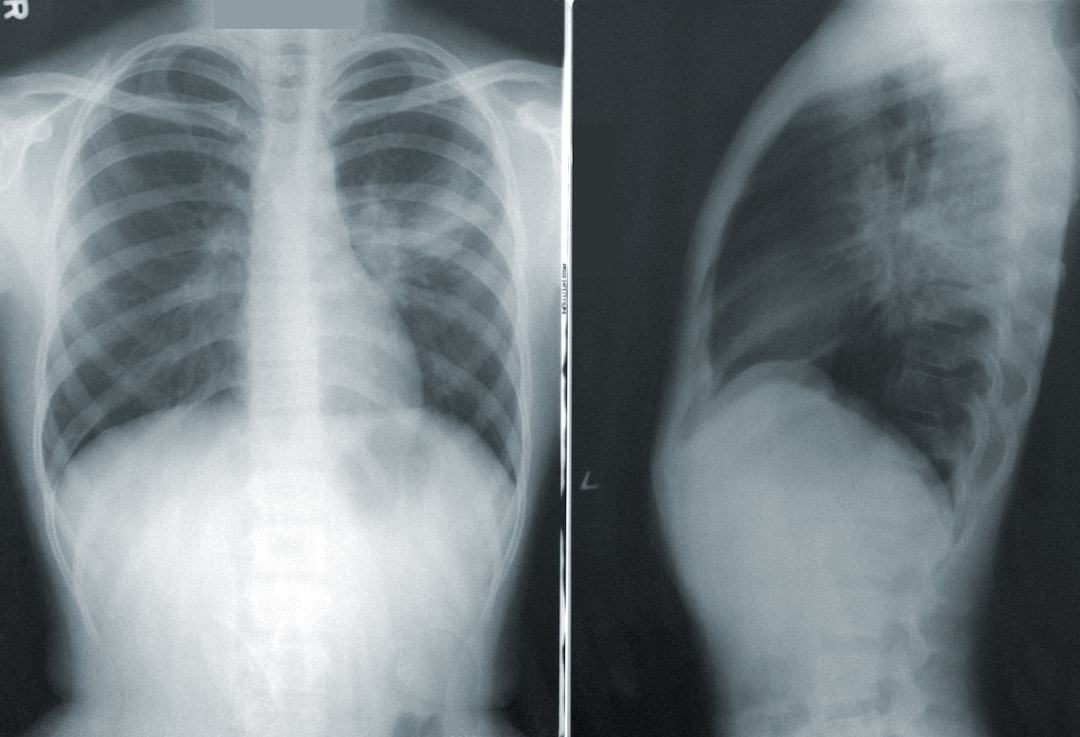

부정맥은 심장이 비정상적으로 뛰는 상태를 말하며, 이는 다양한 증상과 원인을 동반할 수 있습니다. 심장이 너무 빨리 뛰거나 느리게 뛰는 등의 형태로 나타나며, 그로 인해 피로감, 현기증, 가슴 통증 등의 불편함이 초래됩니다. 따라서 부정맥 치료는 개인의 건강을 지키는 데 필수적입니다. 심장 건강을 유지하기 위해서는 정기적으로 검사를 받고, 증상을 체크하며, 전문가의 조언을 따르는 것이 중요합니다.

부정맥의 증상은 매우 다양합니다. 심박 수가 너무 빨라지는 빈맥 부정맥 치료가 필요한 경우에는 두근거림이나 숨 가쁨이 느껴지는 경우가 많으며, 반대로 서맥성 부정맥에서는 피로감과 어지러움이 주요 증상으로 나타납니다. 자신의 증상을 잘 살펴보는 것이 중요합니다. 증상이 심각하다면 즉시 치료를 받아야 하며, 지속적으로 나타난다면 전문의에게 꼭 상담받아야 합니다.

부정맥의 증상은 심장이 어떻게 작용하는지에 따라 다르게 나타납니다. 가슴 통증이나 불편함이 일어나는 경우, 이는 심장 내부의 문제가 생겼다는 신호일 수 있습니다. 이러한 증상이 길어지면 심장 혹은 신체에 더 큰 문제를 일으킬 수 있으므로, 조기 발견과 치료가 절실해야 합니다. 특히 부정맥 치료를 받지 않을 경우 심장병, 뇌졸중 등의 위험이 증가할 수 있습니다.

부정맥의 경우 치료법도 개인별로 상이합니다. 부정맥 치료에는 약물요법, 심장 전기적 치료, 카테터 절제술 등이 포함됩니다. 특히 부정맥 치료약으로는 딜라트렌정 같은 약물이 처방될 수 있습니다. 이러한 치료 방법들은 환자의 상태에 따라 유동적으로 조절되는 만큼, 전문가의 상담을 통해 정확한 진단을 받는 것이 중요합니다. 이를 통해 우리는 적절한 치료 계획을 수립할 수 있습니다.